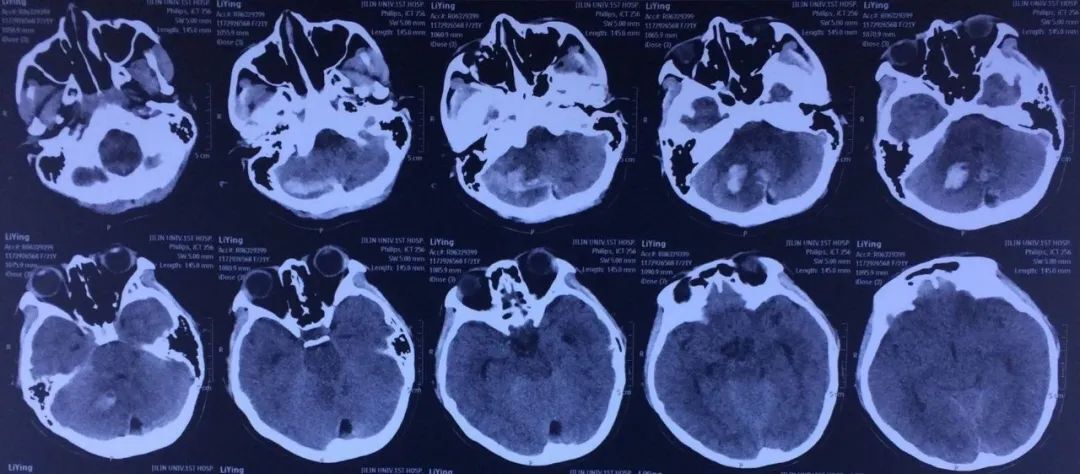

患者李先生,62岁,是一位退休教师。从2018年开始,他逐渐出现了走路不稳、说话不清等症状。经过一系列检查,医生诊断为小脑萎缩。在接受了一段时间的西医治疗之后,李先生的症状并未得到明显改善。于是,他开始寻求中医的帮助。后来在公众号上看到了盛劲强大夫治疗小脑萎缩的效果不错,因不方便来京,于是预约了盛劲强大夫远程视频会诊号位。盛大夫中医辨证为“痿证”采用补髓健脑汤加减药物治疗。

经过了一个疗程的治疗之后,吃饭喝水呛咳的现象明显减轻,失眠多梦偶尔有,眼睛模糊重影减轻,患者见到治疗的效果不错,所以决定继续接受治疗,一共经过六个疗程的治疗之后,呛咳的症状消失,胸闷气短没有了,睡眠正常了,眼睛模糊重影没有了,口齿不清好了,四肢无力也有很大程度的改善,腿抽筋的症状消失了,诸多症状都得到了缓解与改善。随后患者选择了停药观察。